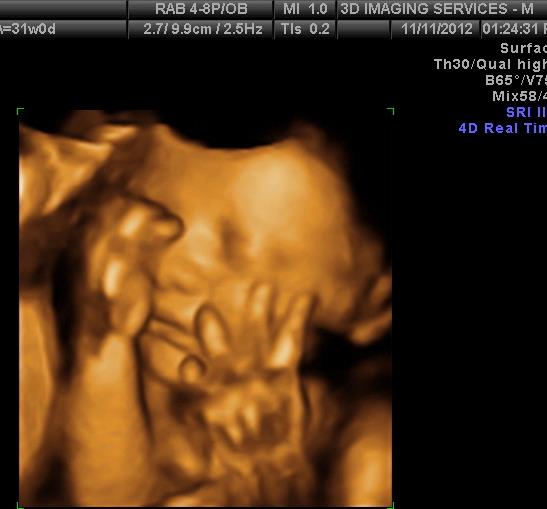

Are 3D Ultrasounds Dangerous . Ultrasounds have moved beyond the grainy, indecipherable images of the past. are 3d ultrasounds safe? yes, 3d ultrasound is not a dangerous imaging test for the foetus, it is completely safe. Here is what a 3d ultrasound looks like: but before you do, it’s important to understand what 3d sonograms and 4d ultrasounds are, when they're used during pregnancy (if at all), how much they cost, and — most importantly — whether they're safe for you and your baby. in other words, 3d sonograms and 4d ultrasounds are not part of routine prenatal exams. if your doctor deems a 3d or 4d ultrasound necessary, there's no cause for concern. Moreover, this test does not pose any danger. the short answer is yes, 3d and 4d ultrasounds are generally considered safe when performed by trained professionals. in most cases, 3d ultrasounds are elective. 3d and 4d ultrasounds are they.

in other words, 3d sonograms and 4d ultrasounds are not part of routine prenatal exams. if your doctor deems a 3d or 4d ultrasound necessary, there's no cause for concern. in most cases, 3d ultrasounds are elective. but before you do, it’s important to understand what 3d sonograms and 4d ultrasounds are, when they're used during pregnancy (if at all), how much they cost, and — most importantly — whether they're safe for you and your baby. Here is what a 3d ultrasound looks like: Ultrasounds have moved beyond the grainy, indecipherable images of the past. yes, 3d ultrasound is not a dangerous imaging test for the foetus, it is completely safe. are 3d ultrasounds safe? 3d and 4d ultrasounds are they. the short answer is yes, 3d and 4d ultrasounds are generally considered safe when performed by trained professionals. Moreover, this test does not pose any danger.